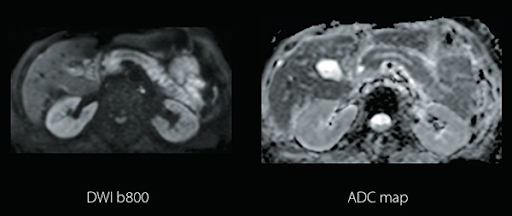

Water Fat Separation обеспечивает однородные изображения с сохранением четырех разных контрастов тканей за одно сканирование, сокращая количество необходимых исследований. Может использоваться для исследования любой части тела.

Технология Quick Star на свободном дыхании уменьшает артефакты движения. Полезна для сложных пациентов, которым трудно задерживать дыхание, особенно при исследовании печени, или недостаточном контакте с пациентом, например в педиатрии.